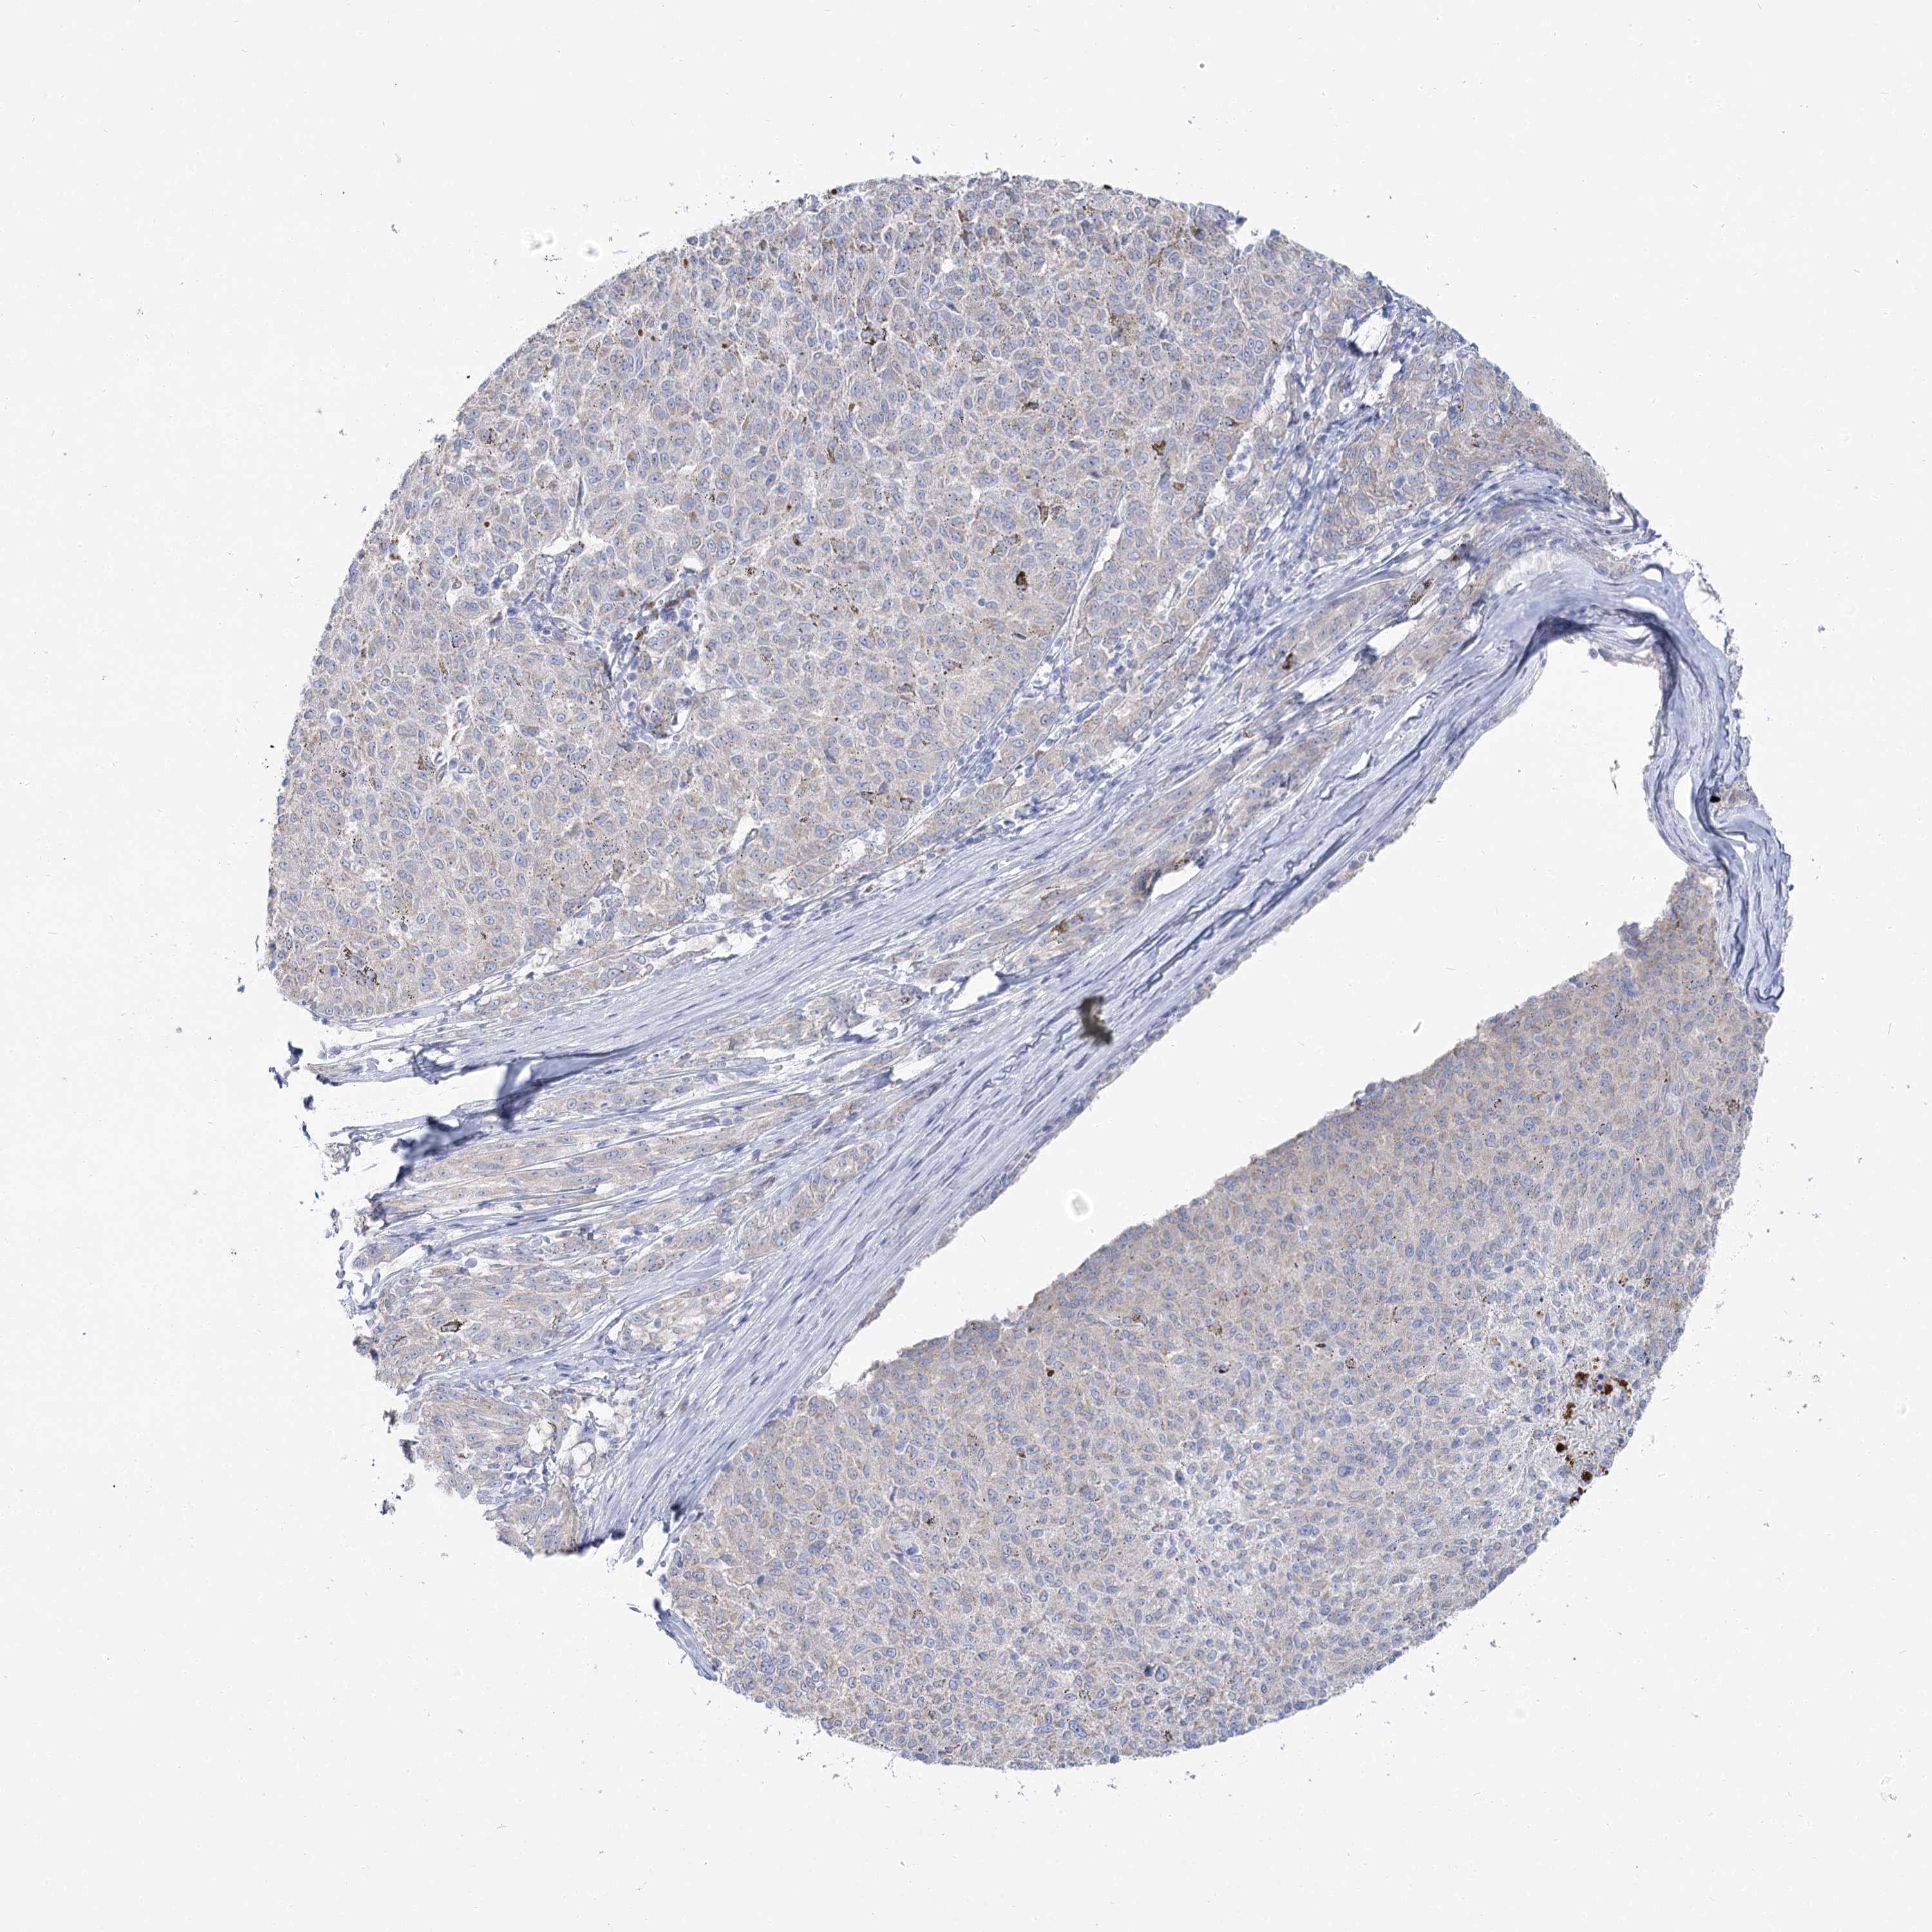

MELANOMA - Protein expressioni

A mouse-over function shows sample information and annotation data. Click on an image to view it in a full screen mode. Samples can be filtered based on level of antibody staining by selecting one or several of the following categories: high, medium, low and not detected. The assay and annotation is described here.

Note that samples used for immunohistochemistry by the Human Protein Atlas do not correspond to samples in the TCGA dataset.

Antibody stainingi

Antibody staining in the annotated cell types in the current human tissue is reported as not detected, low, medium, or high, based on conventional immunohistochemistry profiling in selected tissues. This score is based on the combination of the staining intensity and fraction of stained cells.

Each image is clickable and will lead to virtual microscopy that enables deeper exploration of all samples and also displays staining intensity scores, fraction scores and subcellular localization as well as patient and tissue information for each sample.

Antibody HPA038208

Antibody HPA038209

Staining

High

Medium

Low

Not detected

Intensity

Strong

Moderate

Weak

Negative

Quantity

>75%

75%-25%

<25%

None

Location

Nuclear

Cytoplasmic/membranous

Cytoplasmic/membranous,nuclear

Malignant melanoma, NOS

Malignant melanoma, Metastatic site